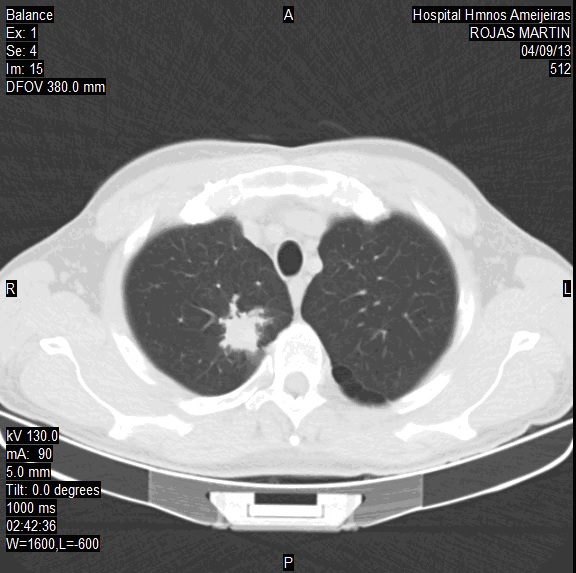

TAC simple de cráneo y tórax, 9 de abril de 2013

Cráneo: no hay signo de metástasis.

Tórax:en la parte interna de vértice derecho nódulo infiltrante que mide 2 x 2,2 cm (imagen 2A).

IMAGEN 2A. TAC de tórax: 9 de abril de 2013